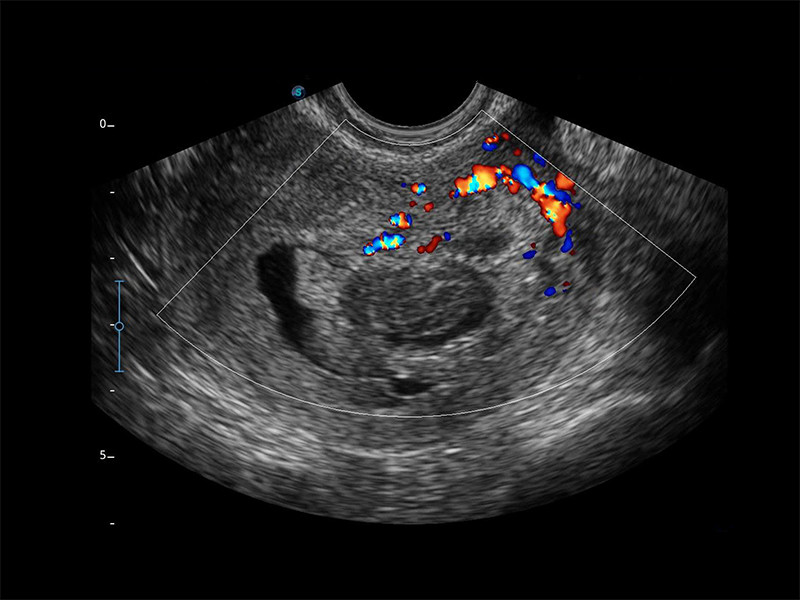

E2 é um sistema de ultrassom Doppler colorido que vai além das suas expectativas devido à sua aparência compacta e moderna. Ele atende aplicações gastrointestinais, obstétricas/ginecológicas, cardíacas e POC para atender às suas necessidades de digitalização de rotina, enquanto seu modo colorido o ajudará a obter um diagnóstico de lesões mais preciso e eficiente. O E2 oferece uma ampla gama de aplicativos para auxiliar os usuários na digitalização de rotina. O E2 fornece cálculos automáticos para aumentar sua confiança no diagnóstico e economizar tempo na comunicação com o paciente.

Fluxo SR

Uma nova tecnologia inovadora, o SR Flow melhora a capacidade de detectar

sinais de fluxo de baixa velocidade, ao mesmo tempo que melhora a resolução

espacial e supera o excesso para apresentar ao usuário informações

hemodinâmicas reais.